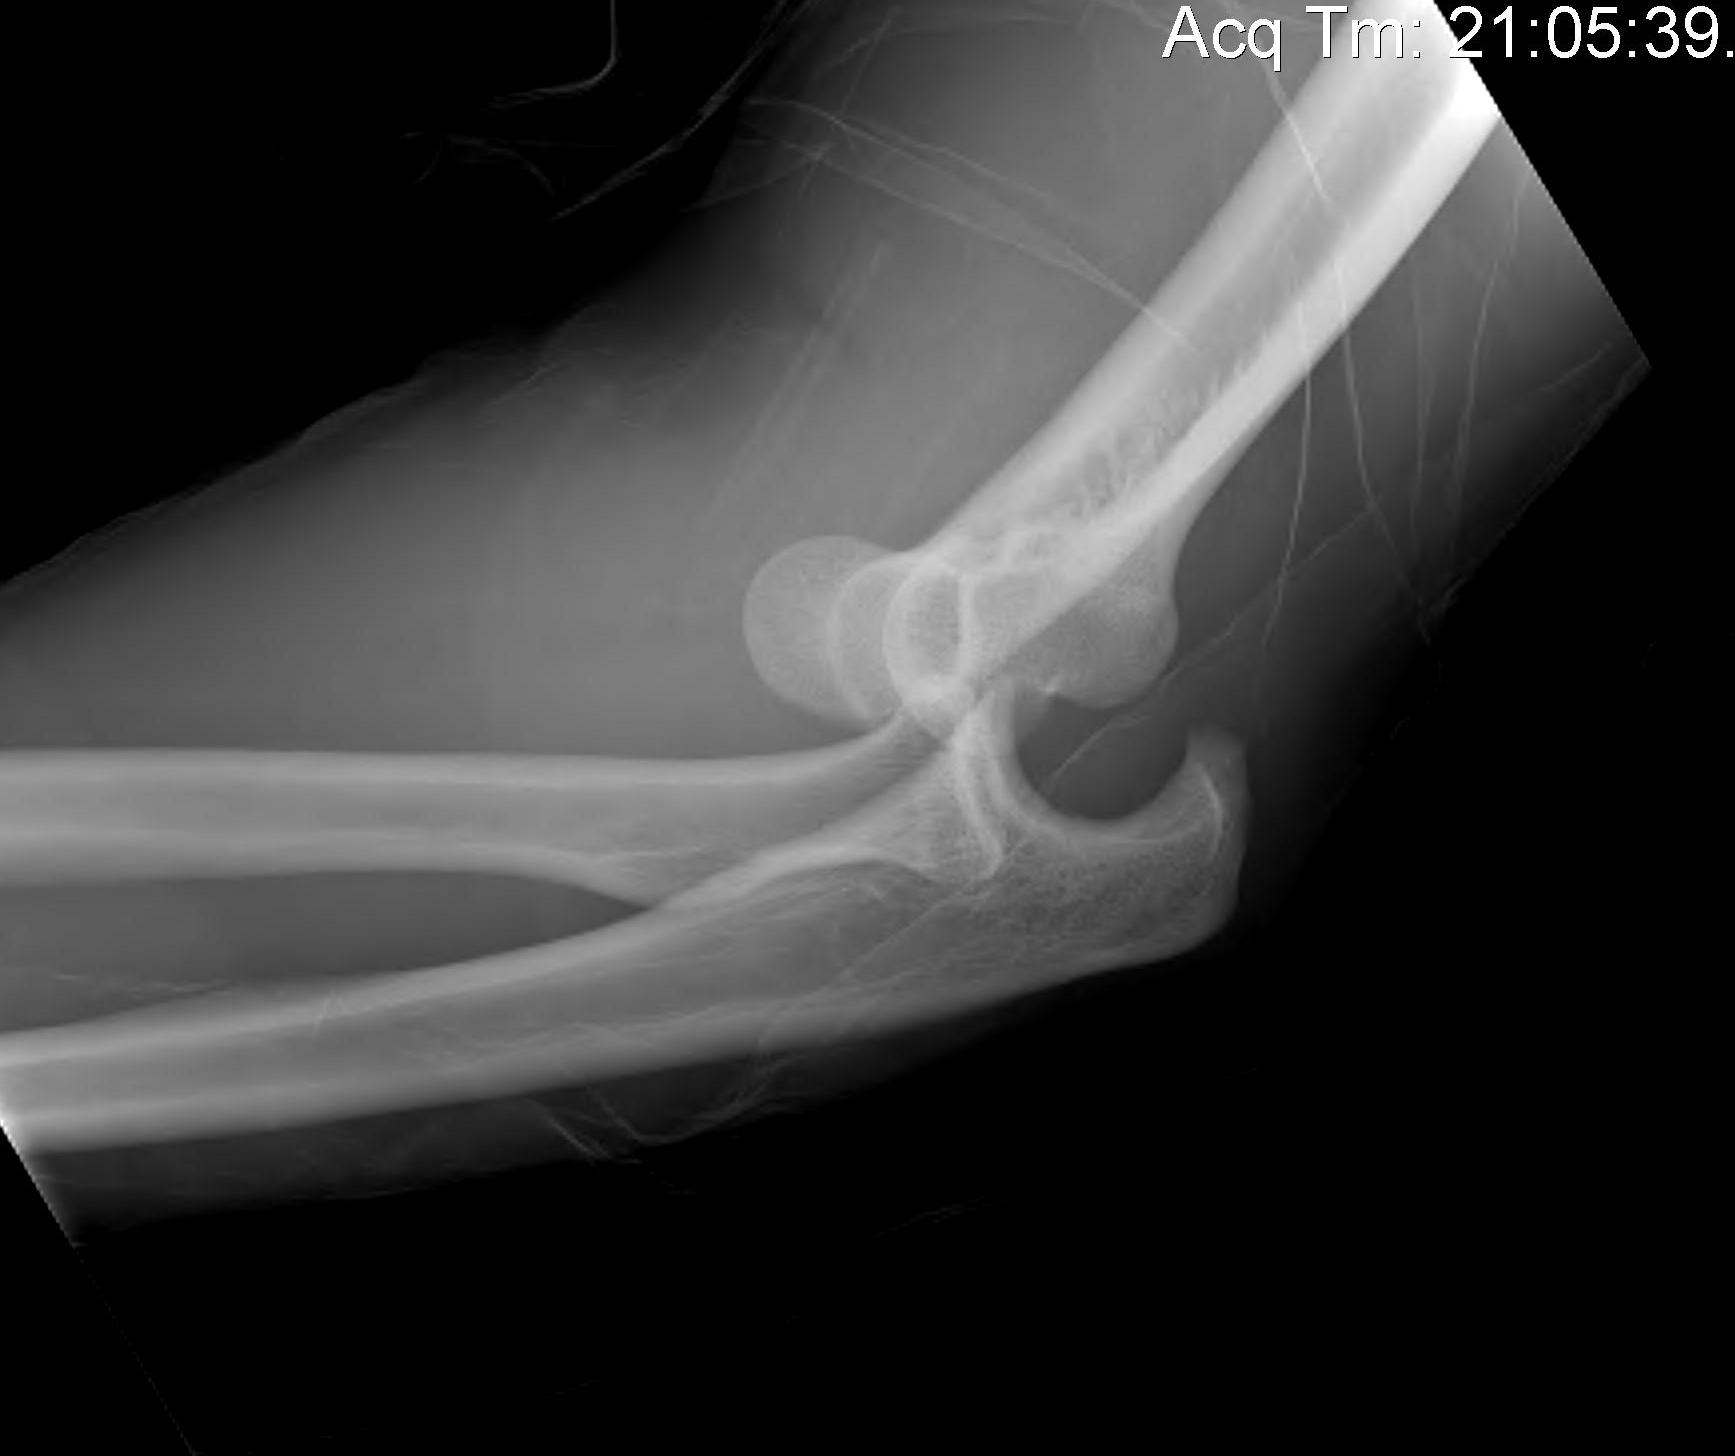

Posterolateral rotatory subluxation / instability

Incomplete posterolateral dislocation Coranoid perches on trochlea |